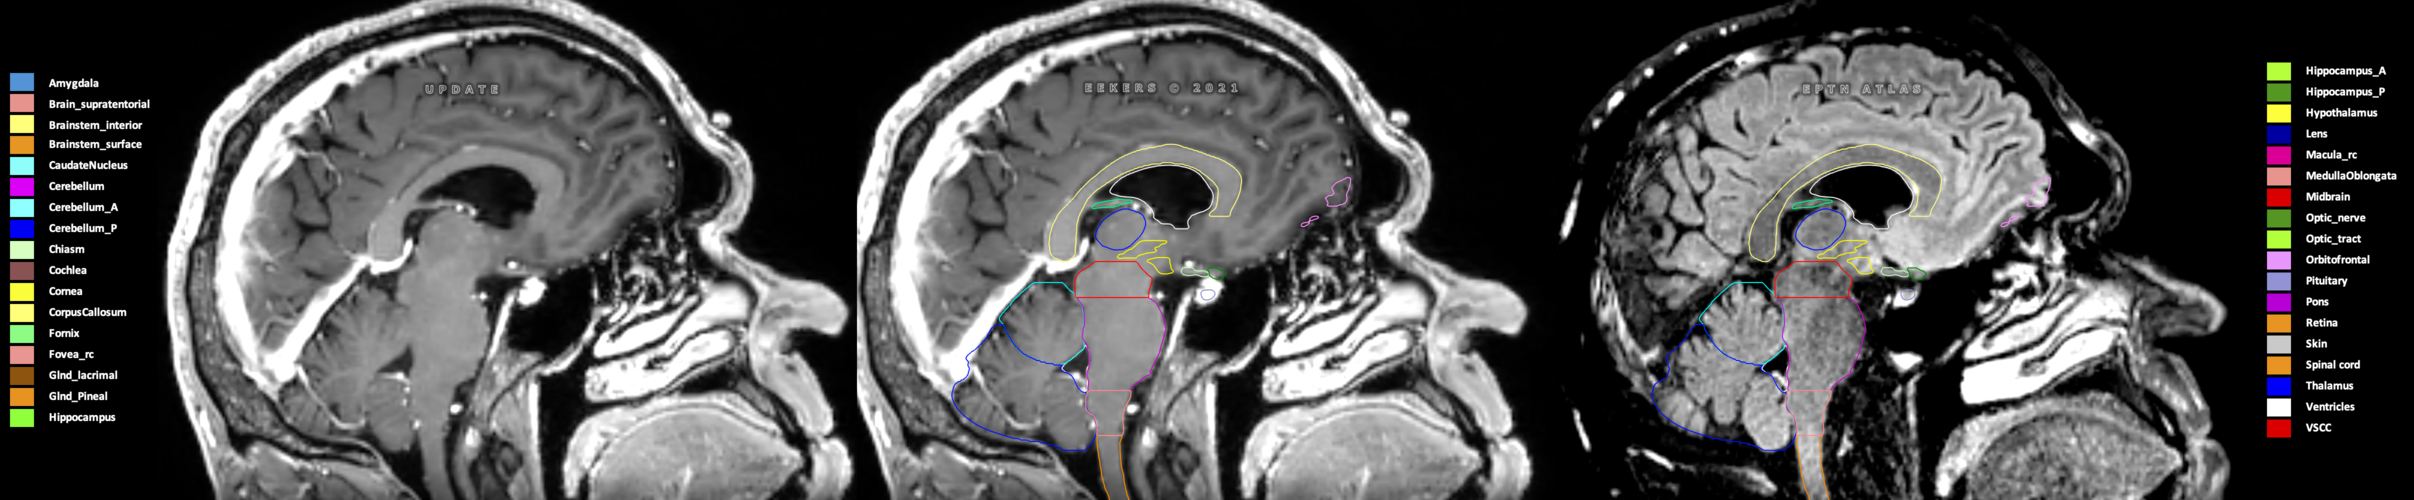

Eekers et al. have published an international neurological atlas for contouring of organs at risk in consensus with the European Particle Therapy Network (EPTN) in 2018 and an update in 2021. The purpose of this consensus atlas is to decrease inter- and intra-observer variability in delineating OARs relevant for neuro-oncology.

Included are all OARs known to be relevant for radiation-induced toxicity in neuro-oncology: brain, brainstem (midbrain, pons, medulla oblongata), chiasm, cerebellum (anterior & posterior), cochlea, cornea, hippocampus (anterior & posterior), hypothalamus, lens, lacrimal gland, optic nerve, pituitary, skin, and vestibular & semicircular canals. To further facilitate research on cognition, vision and radiological changes after irradiation of the brain, potential clinically-relevant OARs are included: amygdala, caudate nucleus, cerebellum (anterior & posterior), corpus callosum, fornix, macula, optic tract, orbitofrontal cortex, periventricular space (PVS), pineal gland, and thalamus.

Three-dimensional delineation of the 25 consensus OARs for neuro-oncology are shown on CT (WW/WL 120/40, 3000/600), 3T MR images, (T1Gd, T2FLAIR 1mm) and 7T MR (MP2RAGE 0.7 mm). All are presented in transversal, sagittal and coronal view.